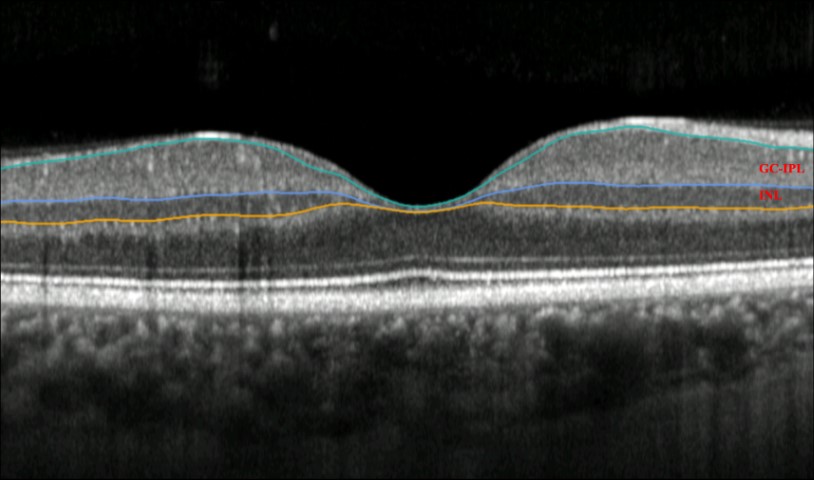

The team, led by Dr Siegfried Wagner and Professor Pearse Keane of Moorfields and UCL Institute of Ophthalmology, found Parkinson’s patients had differences in thickness in their retina’s inner nuclear layer (INL) and ganglion cell-inner plexiform layer (GCIPL). Using artificial intelligence (AI), images from INSIGHT, the world's largest database of retinal images and associated clinical data, were screened for these differences. The team then validated their model using data from the UK Biobank.

An OCT scan of a retina, with the highlighted individual layers

Exploring whether progression of GCIPL atrophy is driven by brain changes in Parkinson’s disease or if INL thinning precedes GCIPL atrophy could help explain the mechanism and determine whether retinal imaging could support the diagnosis, prognosis and complex management of Parkinson’s patients, researchers concluded.